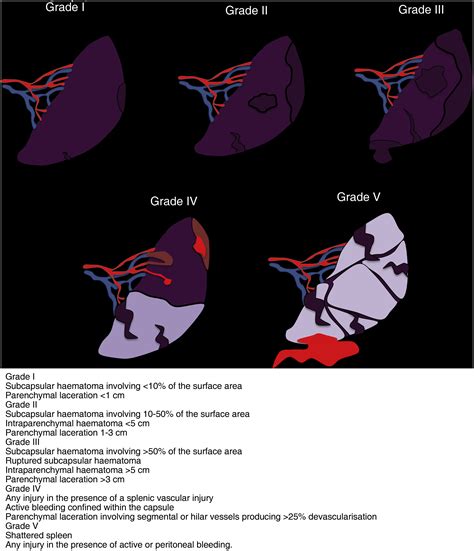

The most commonly used grading system for splenic injuries is the American Association for the Surgery of Trauma (AAST) Organ Injury Scale. This scale categorizes splenic injuries into six grades based on the severity of the laceration.

Grade I

Grade I injuries are the least severe and involve:

• Subcapsular hematoma less than 10% of the surface area.

• Capsular tear less than 1 cm in depth.

Grade II

Grade II injuries are slightly more severe and include:

• Subcapsular hematoma 10-50% of the surface area.

• Capsular tear 1-3 cm in depth.

• Parenchymal laceration less than 1 cm in depth.

Grade III

Grade III injuries are more significant and involve:

• Subcapsular hematoma more than 50% of the surface area or expanding.

• Capsular tear more than 3 cm in depth.

• Parenchymal laceration 1-3 cm in depth.

Grade IV

Grade IV injuries are severe and include:

• Parenchymal laceration more than 3 cm in depth.

• Involvement of a trabecular vessel.

Grade V

Grade V injuries are the most severe and involve:

• Shattered spleen.

• Hilar vascular injury with devascularized spleen.